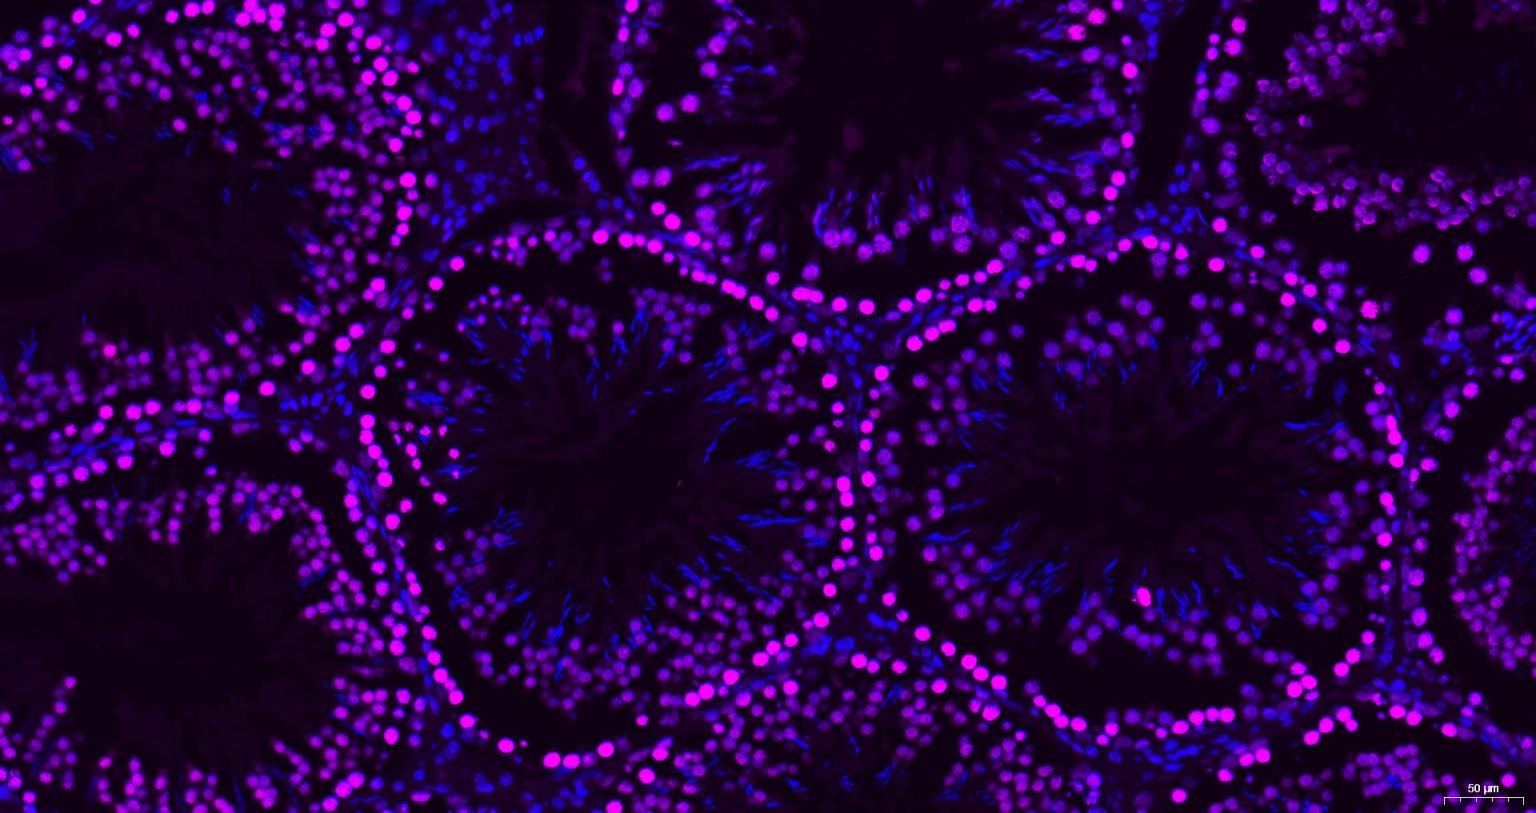

| Verified Activity | 1. Paraformaldehyde-fixed, paraffin embedded Rat Testicles; Antigen retrieval by boiling in sodium citrate buffer (pH6.0) for 15 min; Antibody incubation with Histone H3 Monoclonal Antibody, Unconjugated at 1:200 overnight at 4°C. Followed by conjugated Goat Anti-Mouse IgG antibody (Purple, TMAB-02010C5), DAPI (blue) was used to stain the cell nuclei.

2. Paraformaldehyde-fixed, paraffin embedded Rat Cerebrum; Antigen retrieval by boiling in sodium citrate buffer (pH6.0) for 15 min; Antibody incubation with Histone H3 Monoclonal Antibody, Unconjugated at 1:200 overnight at 4°C. Followed by conjugated Goat Anti-Mouse IgG antibody (Purple, TMAB-02010C5), DAPI (blue) was used to stain the cell nuclei. 3. Paraformaldehyde-fixed, paraffin embedded Mouse Cerebrum; Antigen retrieval by boiling in sodium citrate buffer (pH6.0) for 15 min; Antibody incubation with Histone H3 Monoclonal Antibody, Unconjugated at 1:200 overnight at 4°C. Followed by conjugated Goat Anti-Mouse IgG antibody (Purple, TMAB-02010C5), DAPI (blue) was used to stain the cell nuclei. 4. Paraformaldehyde-fixed, paraffin embedded Human Cerebrum; Antigen retrieval by boiling in sodium citrate buffer (pH6.0) for 15 min; Antibody incubation with Histone H3 Monoclonal Antibody, Unconjugated at 1:200 overnight at 4°C. Followed by conjugated Goat Anti-Mouse IgG antibody (Purple, TMAB-02010C5), DAPI (blue) was used to stain the cell nuclei. 5. Paraformaldehyde-fixed, paraffin embedded Mouse Testicles; Antigen retrieval by boiling in sodium citrate buffer (pH6.0) for 15 min; Antibody incubation with Histone H3 Monoclonal Antibody, Unconjugated at 1:200 overnight at 4°C. Followed by conjugated Goat Anti-Mouse IgG antibody (Purple, TMAB-02010C5), DAPI (blue) was used to stain the cell nuclei. 6. Paraformaldehyde-fixed, paraffin embedded Human Liver; Antigen retrieval by boiling in sodium citrate buffer (pH6.0) for 15 min; Antibody incubation with Histone H3 Monoclonal Antibody, Unconjugated at 1:200 overnight at 4°C. Followed by conjugated Goat Anti-Mouse IgG antibody (Purple, TMAB-02010C5), DAPI (blue) was used to stain the cell nuclei. 7. Paraformaldehyde-fixed, paraffin embedded Human Kidney; Antigen retrieval by boiling in sodium citrate buffer (pH6.0) for 15 min; Antibody incubation with Histone H3 Monoclonal Antibody, Unconjugated at 1:200 overnight at 4°C. Followed by conjugated Goat Anti-Mouse IgG antibody (Purple, TMAB-02010C5), DAPI (blue) was used to stain the cell nuclei. 8. Paraformaldehyde-fixed, paraffin embedded Human Colon; Antigen retrieval by boiling in sodium citrate buffer (pH6.0) for 15 min; Antibody incubation with Histone H3 Monoclonal Antibody, Unconjugated at 1:200 overnight at 4°C. Followed by conjugated Goat Anti-Mouse IgG antibody (Purple, TMAB-02010C5), DAPI (blue) was used to stain the cell nuclei. ![]() ![]() ![]() ![]() ![]() ![]() ![]() ![]() |